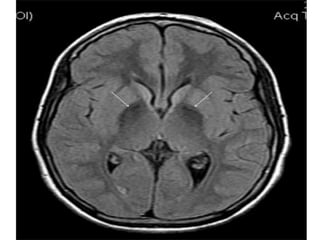

•IMAGINGFOR

PARKINSON’S DISEASE